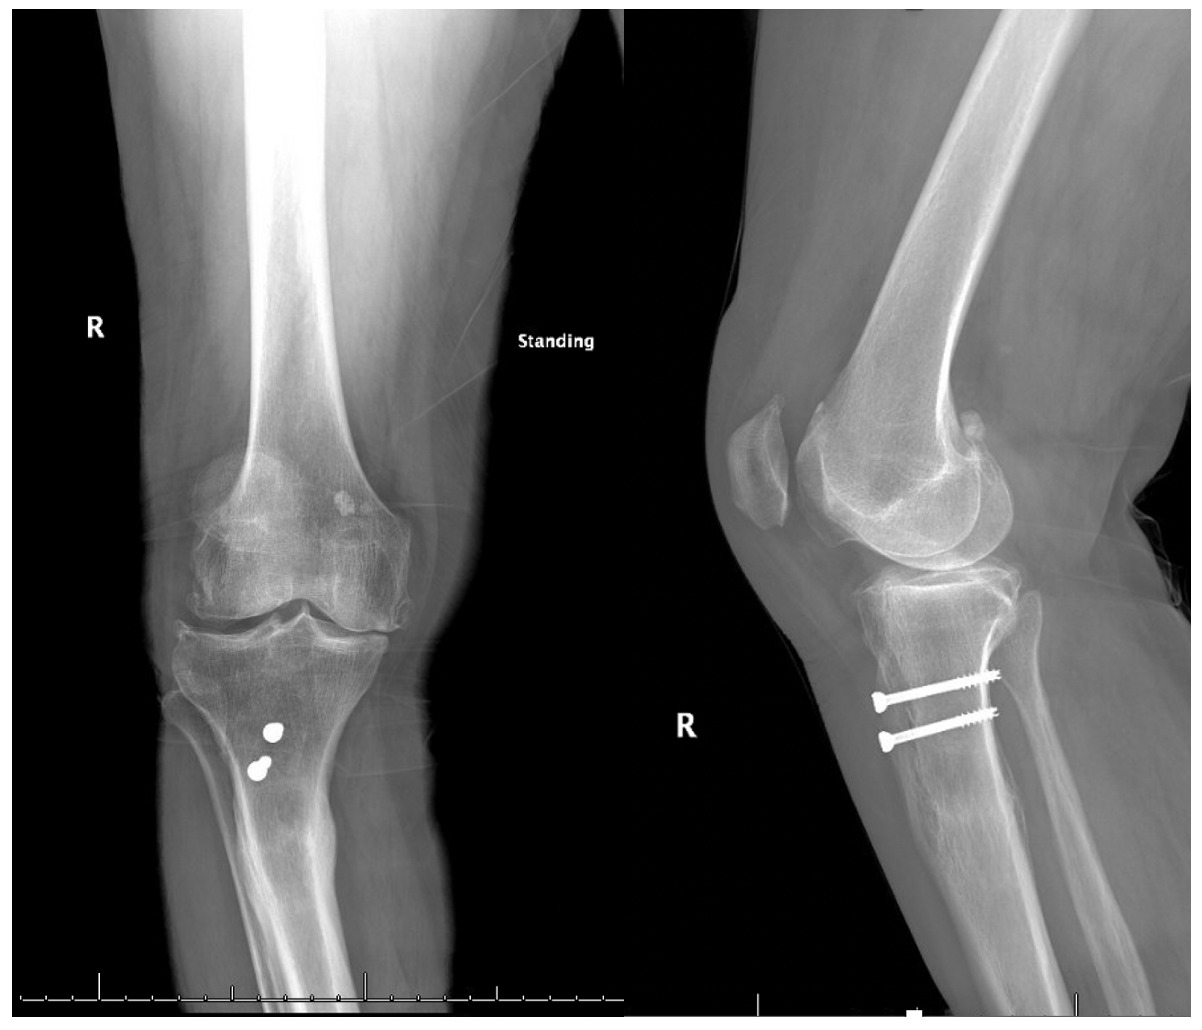

Pre-operative radiographs demonstrated Kellgren-Lawrence grade 4 tricompartmental osteoarthritis, 12° of tibial varus, a 22 mm deviation of the mechanical axis toward the medial side of the knee center, and an apex of angulation located 6 cm below the joint line (Figures 1 and 2). A follow-up computed tomography scan confirmed the absence of rotational malunion.

Physical examination disclosed active knee motion from 0° to 110°, a varus thrust during gait, and patellar subluxation near full extension. The collateral and cruciate ligaments were intact, and neurovascular integrity was preserved. Preoperative patient-reported outcomes included a Knee Society Score of 54 (pain 24, function 30) and a Knee Injury and Osteoarthritis Outcome Score for Joint Replacement (KOOS JR) of 49.

Our patient presented with a borderline deformity: 12° of metaphyseal varus located 6 cm below the joint line. Planning for intra-articular correction suggested an additional 11 mm of medial tibial resection, which would have jeopardized the medial collateral ligament’s attachment and raised the joint line by 4 mm. Given the patient’s high activity goals, the limited options for adjusting joint line elevation (with augment sizes available only in 5 mm, 10 mm, etc.), and the established link between joint line elevation and mid-flexion instability (Laskin 2002), we opted for a single-stage metaphyseal osteotomy stabilized by a long press-fit stem.